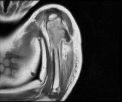

Grafidelezyonun çeperi (korteks) yumurta kabuğu görünümündedir. Düz grafide sabun köpüğü manzarasıtipiktir. Anevrizmal kemik kistinin genişliği metafizden fazladır. Basit kemik kistinin genişliği yakın olan fizden daha büyük değildir. Anevrizmal kemik kisti ile basit kemik kistinin ayırıcı tanısında, MRI’da sıvı-sıvı seviyesi tanı koydurmada yardımcıdır.